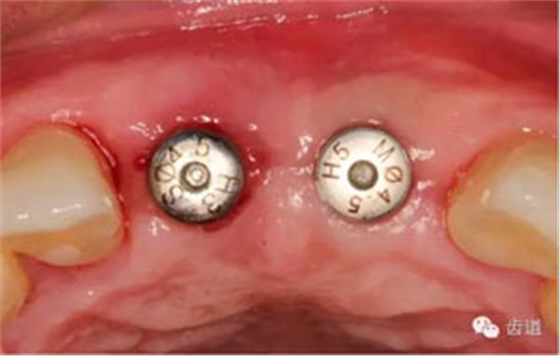

袖口形態(tài)

基臺(tái)就位